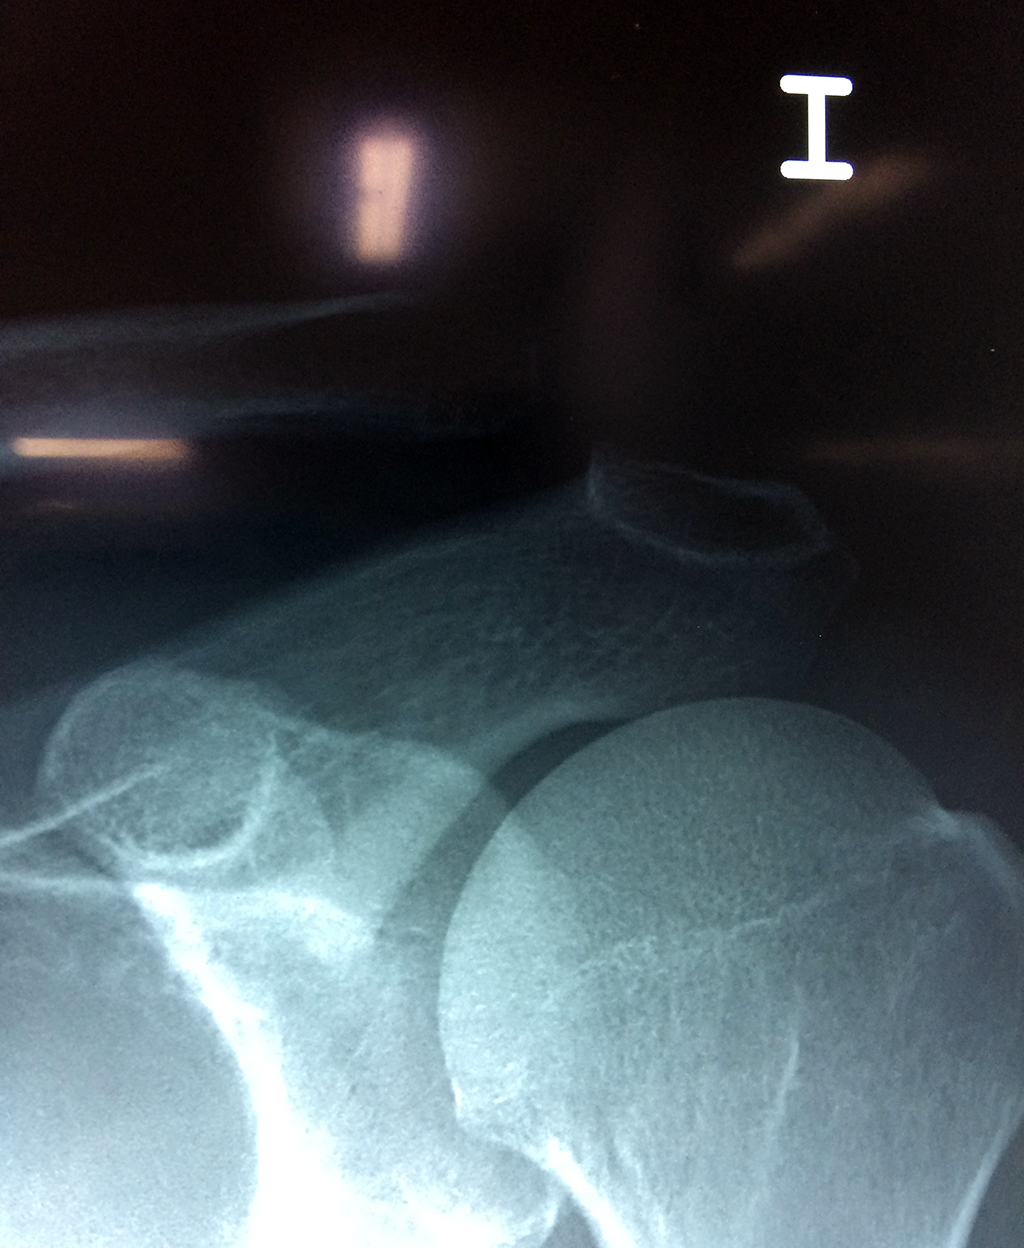

Cirugias en El Salvador - Clavícula

La clavícula es un hueso largo, con forma de "S" itálica, situado en la parte anterosuperior del tórax. Junto con la escápula forman la cintura escapular. Se puede palpar por toda su longitud y se extiende del esternón al acromion de la escápula, siguiendo una dirección oblicua lateral y posterior.